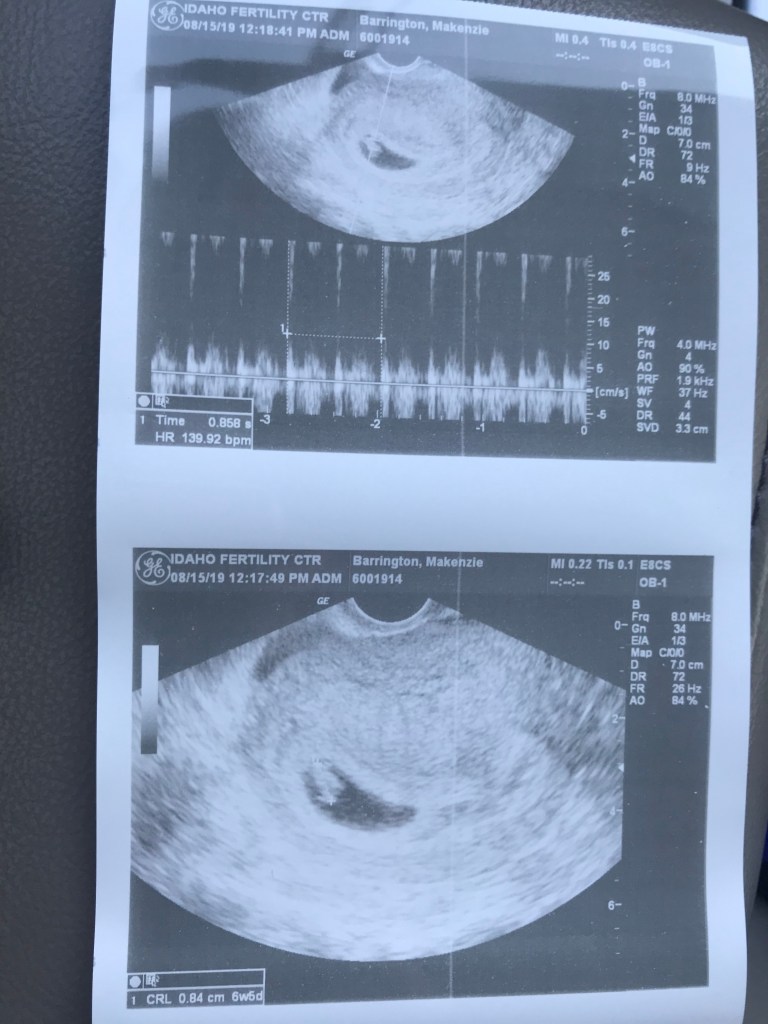

With IVF you stay with the fertility clinic until you reach 9 weeks. Your first ultra sound is at 7 weeks, which is 4 weeks after your blood draw pregnancy test.

The nurse finally came back in and said we’d likely be able to hear the heart beat at this ultrasound but not always.

I laid there watching the screen “we have a baby” as a dark spot showed up in the screen. And there it was…the heartbeat

I will never forget that sound. The fast beating of his little heartbeat. I was still in shock of everything happening. My mom was crying. I just keep staring at the screen trying to wrap my head around the fact that this little blob was my baby!!